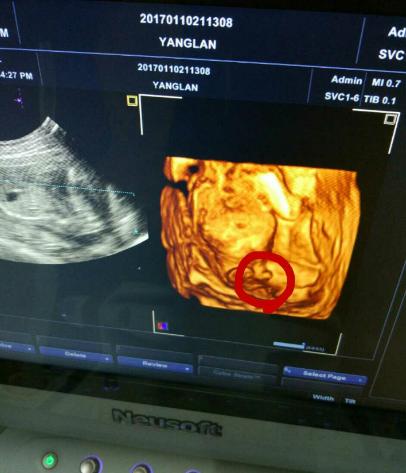

四维彩超宝宝开心 (四维彩超顺利通过宝宝很配合)

朋友怀孕几个月了,每隔一段时间就去检查。迫切地想知道肚子里是个“小鸡妞”,还是“小鸡仔”。前两天又去医院做了唐氏筛查,医院刚好新进了四维机,说是能看到辨别宝宝的性别,朋友兴奋的不得了,于是赶快做了一个检查。第一次看到宝宝动,好激动,医生很仔细的帮看,老公也在看,医生看大腿小鸡鸡好明显,我老公说小鸡鸡耶,医生说看到没有凸起来的那个就是小鸡鸡,朋友说:“听到自己肚子里是个小鸡仔的时候,眼泪不自觉地流了下来。”